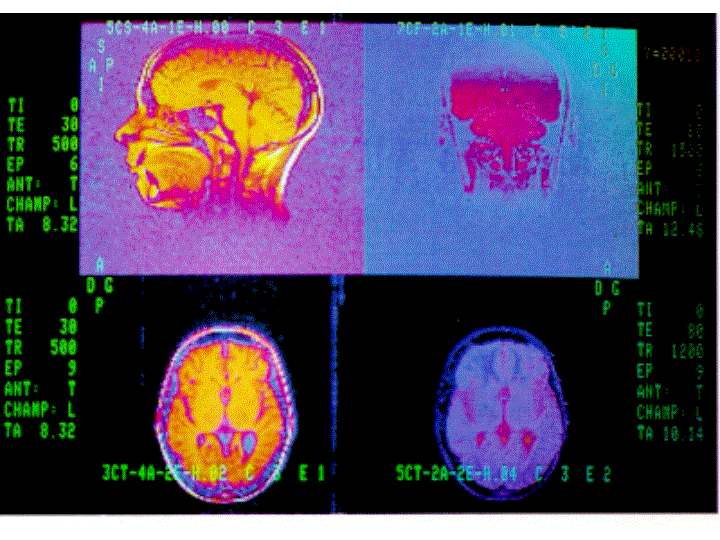

Le tecniche di visualizzazione cerebrale consentono di studiare i rapporti tra struttura cerebrale e funzioni comportamentali: